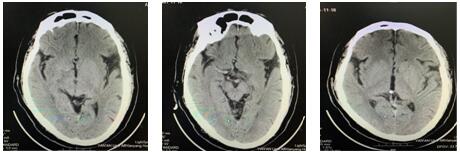

16:26急查頭顱CT示:右側額葉皮質區急性期腦梗死,結合患者癥狀體征考慮腦梗死急性期。請示NICU王偉偉主任,立即啟動綠色通道。